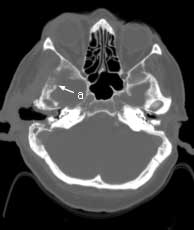

Axial CT bone windows

Findings:

Extensive, permeative destruction involving the squamous portion of the right temporal bone (a). Post-op bilateral mastoidectomies (b).